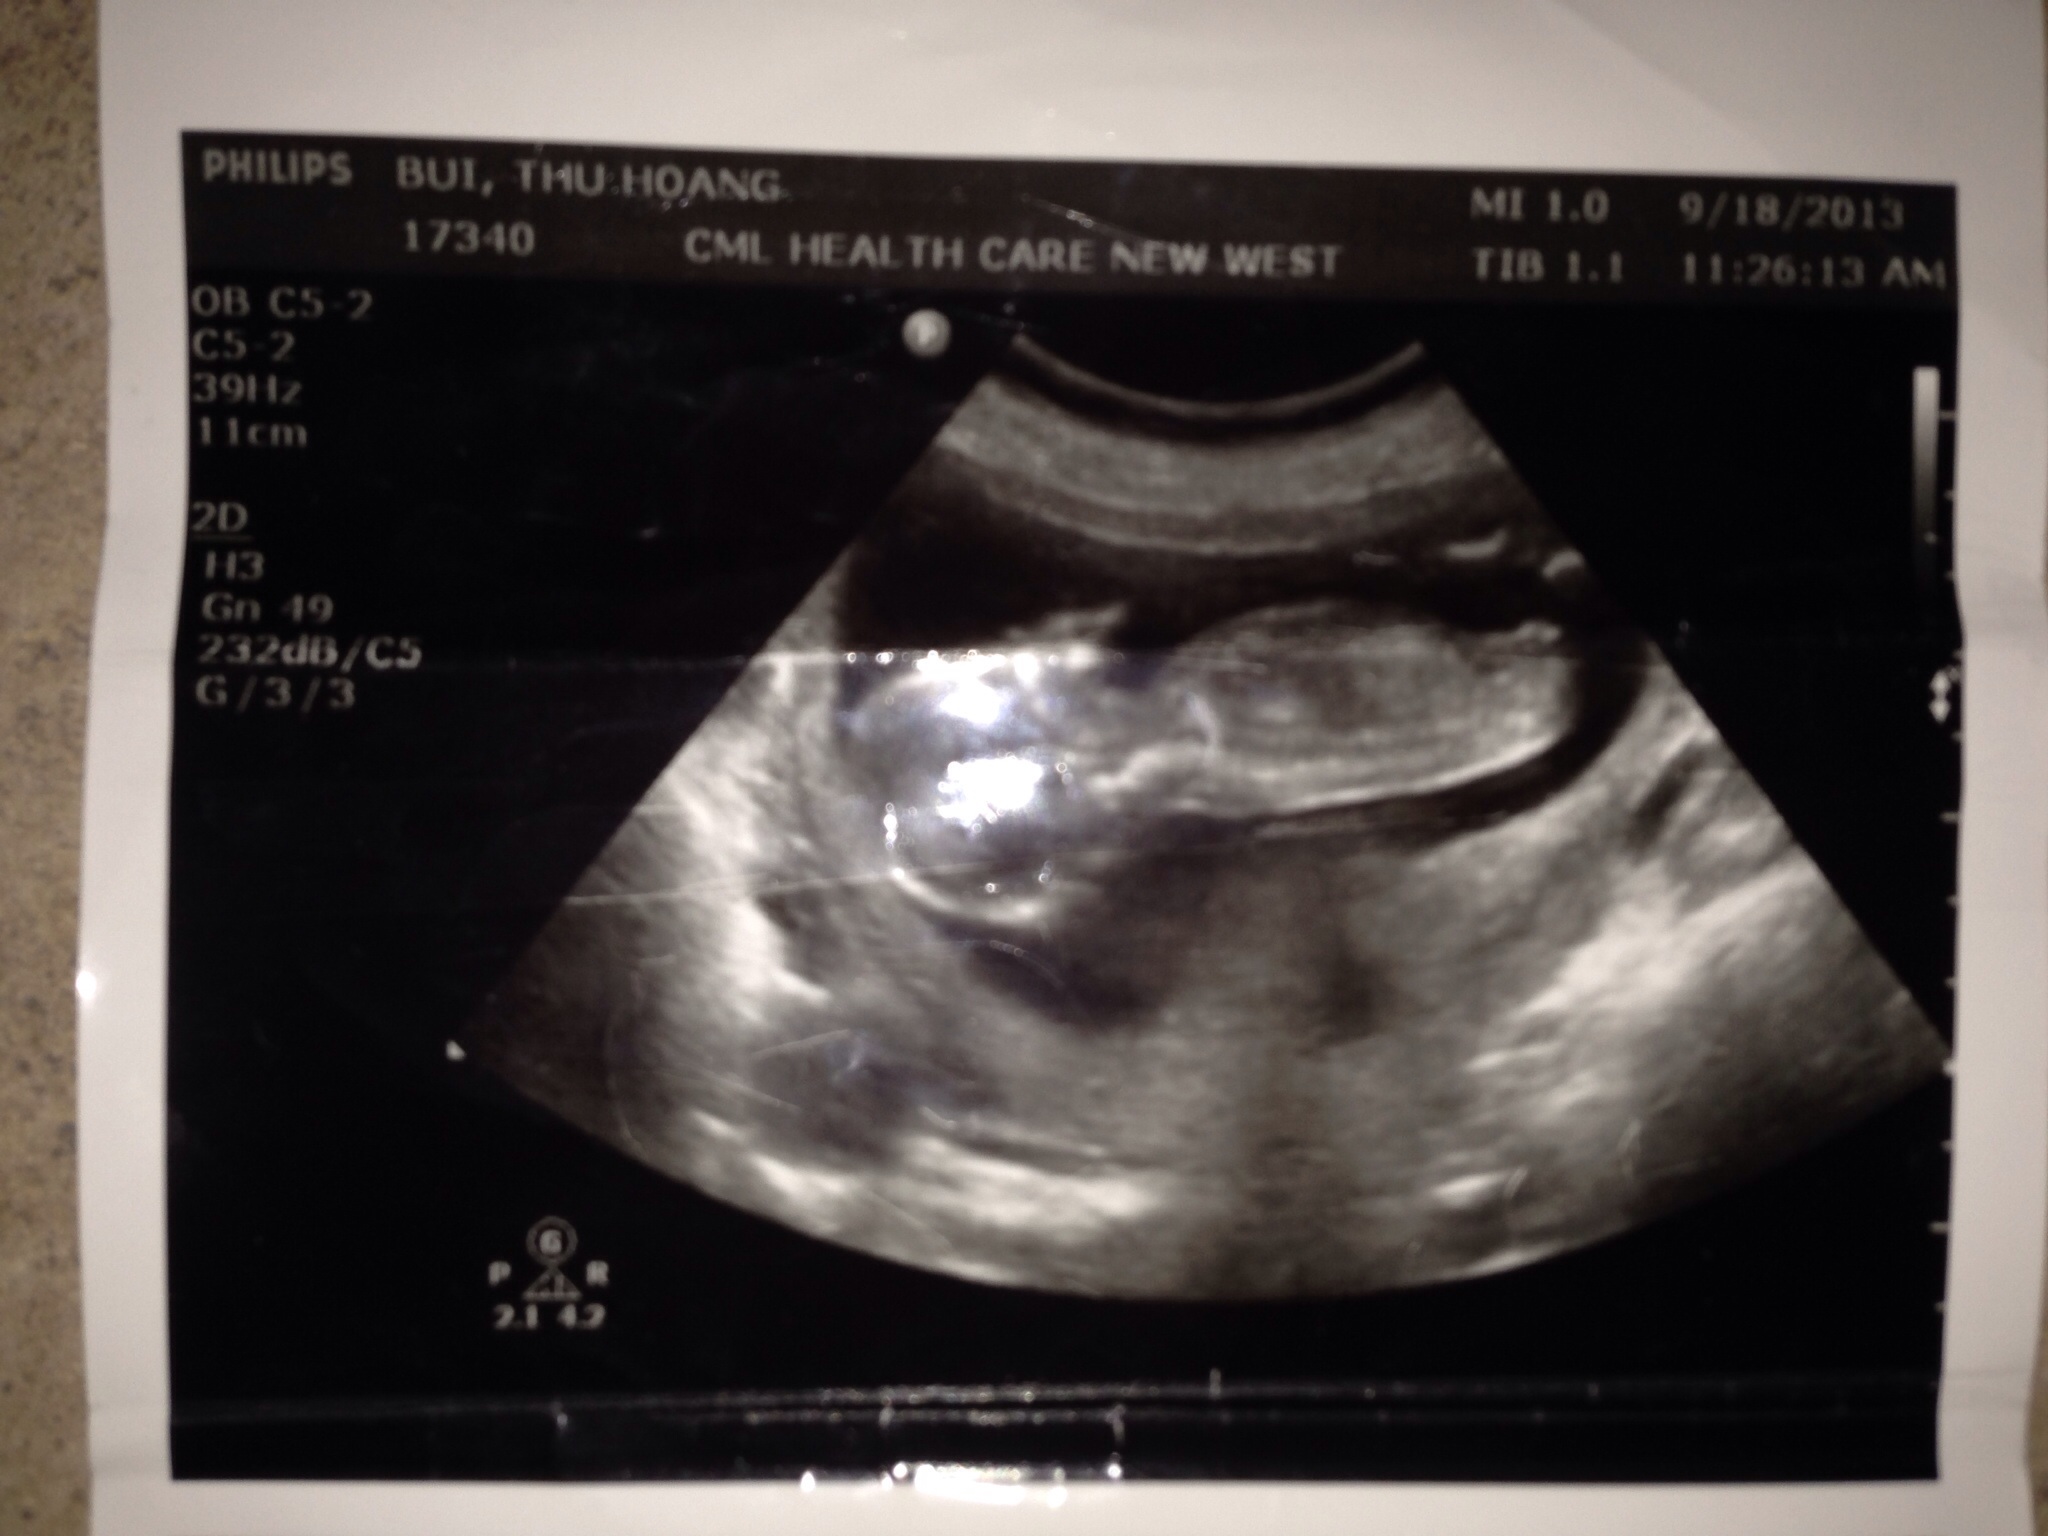

So I put up my baby u/s pic yesterday, but most ppls say they don't see a nub on my pic. I thought I see it quite clear :(:(or it's just my imagination??If you do see it please help me take a guess boy/girl. Much appreciated. Baby is at 13 weeks 5 days

Attachment 14552